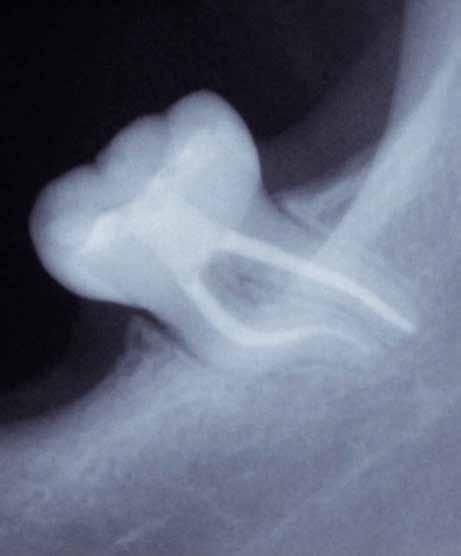

Gyökéramputációt főként a furkáció érintett nagyőrlő fogak ellátása során szoktunk alkalmazni. Derks és mtsai. vizsgálatában a gyökéramputált nagyőrlő fogak közel 80%-a 20 évvel a beavatkozás elvégzését követően is megtartott volt. 1998 októberében egy 39 éves férfi páciens a jobb alsó kvadránsban jelentkező ínyérzékenység miatt kereste fel rendelőnket. A klinikai vizsgálat során jobb alsó első és második nagyőrlő fog között (46–47) nagy kiterjedésű csontveszteséget észleltünk. Ettől eltekintve a teljes fogazat parodontális státusza megfelelőnek bizonyult. A jobb alsó kvadránsban végzett szenzibilitás vizsgálat során arra az eredménye jutottunk, hogy a 46-os fog vélelmezhetően elhalt (10. ábra).

A páciens beleegyezését követően a 46-os fog disztális gyökere, a disztális gyökér felett lévő koronális rész megőrzése mellett rezekcióra került (11. ábra). A rezekciót követően a referáló orvos a 46. és 47. fogak koronáját Ribbond szalag és kompozit segítségével egymáshoz rögzítette. A sebészi beavatkozást követően 22 évvel készült kontrollfelvételen a lézió csontos telődése, kortikális csontállomány kialakulása, valamint a furkáció körüli csontos regeneráció volt megfigyelhető (12. ábra) A károsodott fogak megtartására szolgáló lehetőségek fejlődésének, valamint az implantátumok behelyezésével kapcsolatos rizikófaktorok jobb megértésének köszönhetően ma már más szemmel vizsgáljuk a fogak eltávolításának szükségességét. A kérdéses prognózissal vagy a kis protetikai értékkel rendelkező fogak eltávolítása előtt mindig érdemes felmérni az ezzel elérhető lehetséges előnyök nagyságát. A kemény- és lágyszöveti pótlás lehetőségeinek fejlődésével, a PRF elérhetőségével, a minimálinvazív sebészeti módszerek és az operációs mikroszkópok elterjedésével, valamint a varróanyagok és varrat technikák egyre kifinomultabbá válásával ma már alaposan el kell gondolkodnunk az előtt, hogy egy fogat egy implantátum behelyezése érdekében eltávolítsunk. Mára sokkal kedvezőbb prognózist és sokkal nagyobb sikerességet tudunk elérni a korábban menthetetlennek gondolt fogak kezelése során.